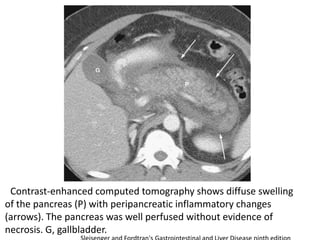

Contrast-enhanced computed tomography shows diffuse swelling

of the pancreas (P) with peripancreatic inflammatory changes

(arrows). The pancreas was well perfused without evidence of

necrosis. G, gallbladder.